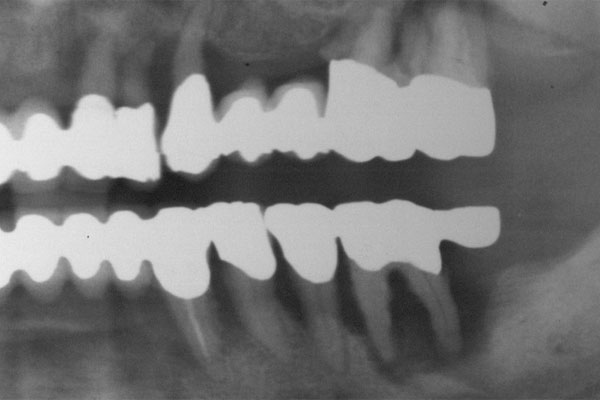

So vielfältig die Ursachen so weitreichend muss die Planung für die Implantologie sein. Alle Disziplinen der Zahnheilkunde sowie allgemeinmedizinische Aspekte sind zu betrachten. Ursachen (Nichtanlage, Unfall, Karies und Parodontitis)

Nichtanlage

Unfall

Karies

Parodontitis